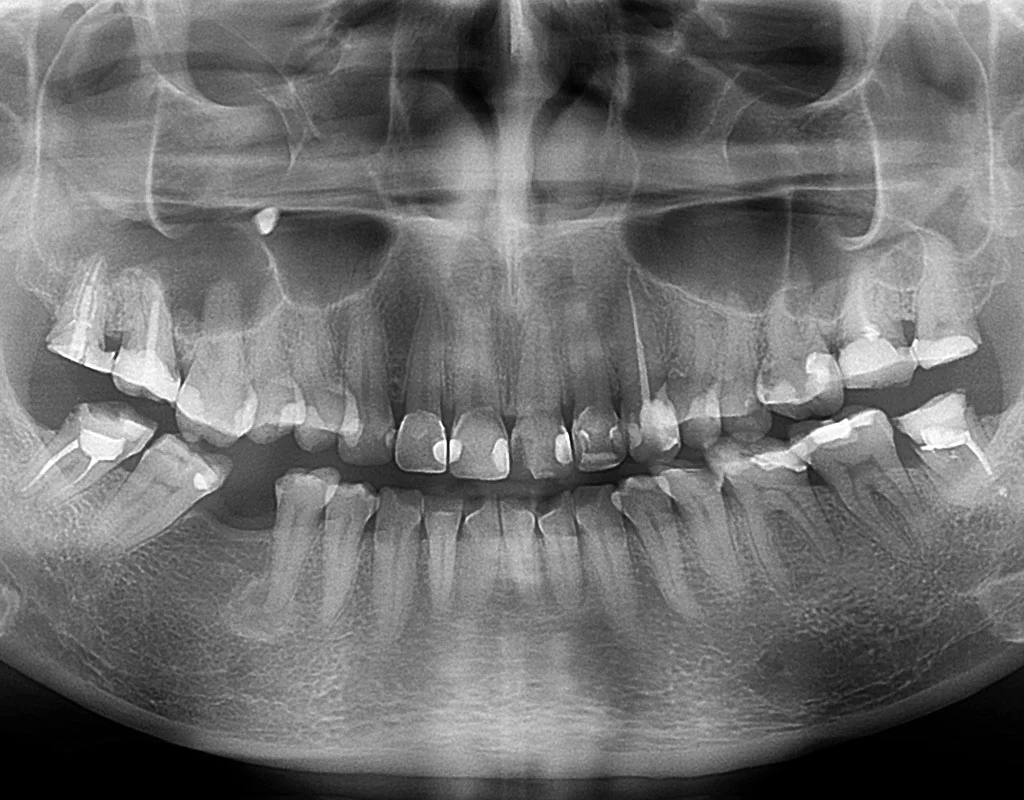

What is a Dental X-Ray?